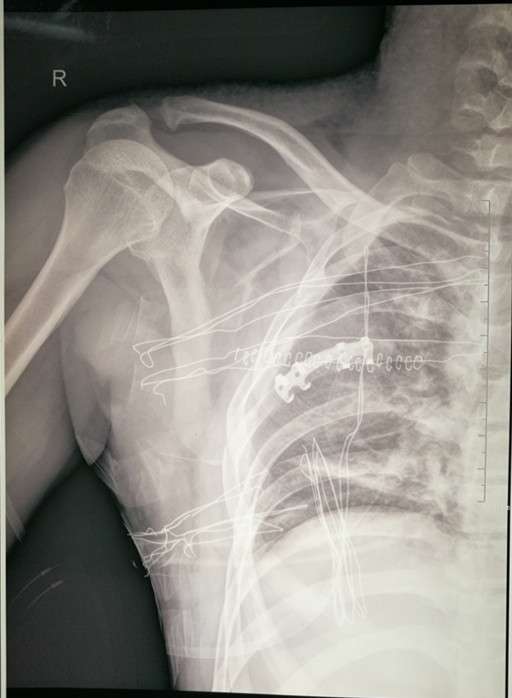

2017年8月22日,我院骨四科燕飞主任医师于肩关节镜下成功完成了一例喙锁韧带重建术治疗肩锁关节脱位,患者男性、47岁,外伤后右肩部疼痛入院,入院后经相关检查,诊断为:右肩锁关节脱位,燕飞主任医师在详细询问病史、进行相关查体后决定行肩关节镜下喙锁韧带重建术治疗肩锁关节脱位,手术过程顺利,术后患者功能恢复良好。现就肩关节镜下喙锁韧带重建术治疗肩锁关节脱位的相关知识介绍如下:

肩锁关节脱位为肩部常见损伤,临床上症状、体征明显,根据 X 线片可基本得到明确诊断。AO锁骨钩钢板是治疗肩锁关节脱位的经典方法,也是基层医院广泛使用的固定方式。但长期随访发现,锁骨钩钢板术后影响肩关节的外展活动,形成肩关节撞击综合征;因应力遮挡产生肩峰下骨质溶解等并发症;同时取出钢板后还可能并发再次脱位的风险。随着微创理念的不断深入以及关节镜技术的快速普及,关节镜技术在肩锁关节脱位的微创治疗中逐渐得到推广,其有效性及安全性不断得到验证。

关节镜辅助或全关节镜下治疗肩锁关节脱位临床疗效得到了认可。Endobutton带袢钢板最初用于膝关节前后交叉韧带的重建。Struhl首次使用Endobutton带袢钢板技术重建喙肩韧带并取得良好的效果。此后逐渐得到推广。在一项长达 11 年的研究结果显示,双 Endobutton 带袢钢板能有效恢复急性和慢性肩锁关节脱位的稳定性,获得良好的临床疗效和影像学表现。

关节镜辅助使用双Endobutton带袢钢板治疗肩锁关节脱位,创伤小,恢复快,有利于损伤的韧带和韧带充分愈合和瘢痕化;通过袢及钢板,在锁骨端和喙突基底形成垂直方向的刚性稳定结构,使锁骨远端足够稳定在解剖位置,使得肩锁、喙锁韧带在肩锁关节稳定的情况下瘢痕愈合;关节镜辅助治疗时还能对肩关节的损伤一并处理;Endobutton 带袢钢板组织相容性好,无需要再次手术取出,减少二次手术带来的创伤和经济负担。